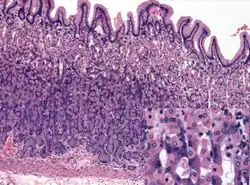

Microanatomy

Wall

Like the other parts of the gastrointestinal wall, the human stomach wall from inner to outer, consists of a mucosa, submucosa, muscular layer, subserosa and serosa.[19]

The inner part of the stomach wall is the gastric mucosa a mucous membrane that forms the lining of the stomach. The membrane consists of an outer layer of columnar epithelium, a lamina propria, and a thin layer of smooth muscle called the muscularis mucosa. Beneath the mucosa lies the submucosa, consisting of fibrous connective tissue.[20] Meissner's plexus is in this layer interior to the oblique muscle layer.[21]

Outside of the submucosa lies the muscular layer. It consists of three layers of muscular fibres, with fibres lying at angles to each other. These are the inner oblique, middle circular, and outer longitudinal layers.[22] The presence of the inner oblique layer is distinct from other parts of the gastrointestinal tract, which do not possess this layer.[23] The stomach contains the thickest muscular layer consisting of three layers, thus maximum peristalsis occurs here.

Glands

The mucosa lining the stomach is lined with gastric pits, which receive gastric juice, secreted by between 2 and 7 gastric glands. Gastric juice is an acidic fluid containing hydrochloric acid and digestive enzymes.[24] The glands contains a number of cells, with the function of the glands changing depending on their position within the stomach.

Within the body and fundus of the stomach lie the fundic glands. In general, these glands are lined by column-shaped cells that secrete a protective layer of mucus and bicarbonate. Additional cells present include parietal cells that secrete hydrochloric acid and intrinsic factor, chief cells that secrete pepsinogen (this is a precursor to pepsin- the highly acidic environment converts the pepsinogen to pepsin), and neuroendocrine cells that secrete serotonin.[25]

Glands differ where the stomach meets the esophagus and near the pylorus.[26] Near the gastroesophageal junction lie cardiac glands, which primarily secrete mucus.[25] They are fewer in number than the other gastric glands and are more shallowly positioned in the mucosa. There are two kinds - either simple tubular glands with short ducts or compound racemose resembling the duodenal Brunner's glands. Near the pylorus lie pyloric glands located in the antrum of the pylorus. They secrete mucus, as well as gastrin produced by their G cells.[27]